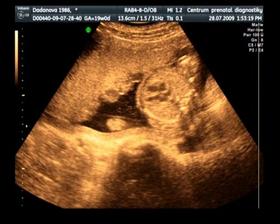

Naše maličké